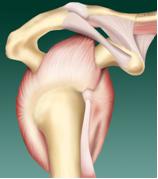

La cuffia dei rotatori è una struttura fondamentale per il funzionamento della spalla, costituita dai tendini di quattro muscoli che originano dalla scapola e si inseriscono sulla testa dell’omero. Anteriormente vi è il sottoscapolare; superiormente il sovraspinoso (o sovraspinato); posteriormente il sottospinoso (o sottospinato) e il piccolo rotondo. I tendini della cuffia convergono a formare una lamina continua, larga parecchi centimetri. Solo tra sottoscapolare e sovraspinoso vi è un sottile interstizio nel quale passa il tendine del capo lungo del bicipite (fig. 1).

Semplificando le loro complesse funzioni si può dire che i quattro muscoli, contraendosi in maniera coordinata, mantengono la testa dell’omero compressa e centrata contro la glena, cioè la superficie articolare della scapola. Questa funzione è indispensabile perché l’articolazione scapolo-omerale non ha una stabilità legata all’incastro delle due componenti (la concavità della glena è appena accennata, molto aperta). Senza l’attività coordinata della cuffia i movimenti di elevazione del braccio diventano impossibili. La seconda principale funzione della cuffia è di muovere la spalla in rotazione interna (il gesto con cui portiamo la mano sull’addome o dietro la schiena) ed esterna (mano in fuori o anche mano sul capo e dietro la nuca). La faccia interna della cuffia dei rotatori riveste l’articolazione della spalla. La faccia esterna invece superiormente è ricoperta da una ampia borsa, una sorta di cuscinetto che evita l’attrito con il piano osseo dell’acromion.